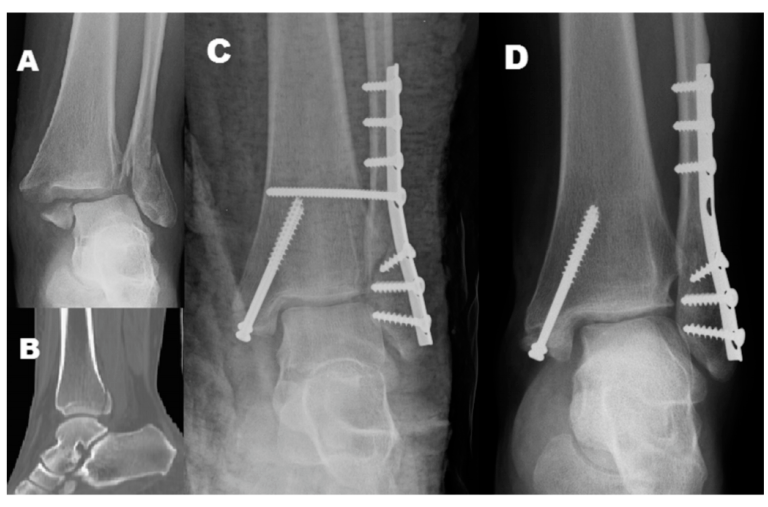

对合并下胫腓联合损伤的内外踝骨折或三踝骨折,常规置入下胫腓螺钉,同时为避免螺钉断裂,恢复下胫腓微动,术者常规在术后6-8周或术后3月取下胫腓螺钉,但下胫腓螺钉取去存在下胫腓不稳风险。为研究双踝/三踝骨折下胫腓螺钉取出的最佳时机,及未固定的后踝与下胫腓稳定性的关系,有学者进行了相关研究,结果发表在近期Injury期刊上。

Lauge-Hansen分型与Danis-Webe分型为最常见的踝关节骨折分型,在对下胫腓韧带损伤的指导意义上,旋后外旋II°骨折通常认为合并下胫腓前韧带的损伤,下胫腓联合趋于稳定,可能无需下胫腓联合螺钉固定。而Danis-Weber B型骨折定义为骨折位于下胫腓联合水平,可能合并下胫腓联合损伤。